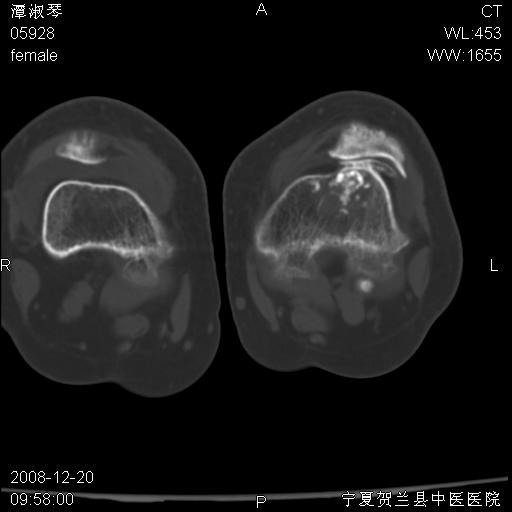

标题: CT17526:请各位看看是啥? [打印本页]

标题: CT17526:请各位看看是啥?

支持骨梗死,退行性骨关节病,膝关节积液.

考虑骨梗死可能性大

骨梗死可能性大

左股骨下段骨梗死。双膝退变。

左胫骨下端松质骨及髓腔内可见点片状高密度灶,骨皮质无明显膨胀及变薄。病变范围较长。支持骨梗死,退行性骨关节病,膝关节积液